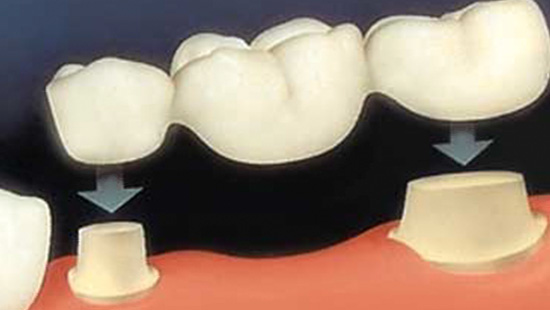

Стоматология: коронки и мостовидные протезы